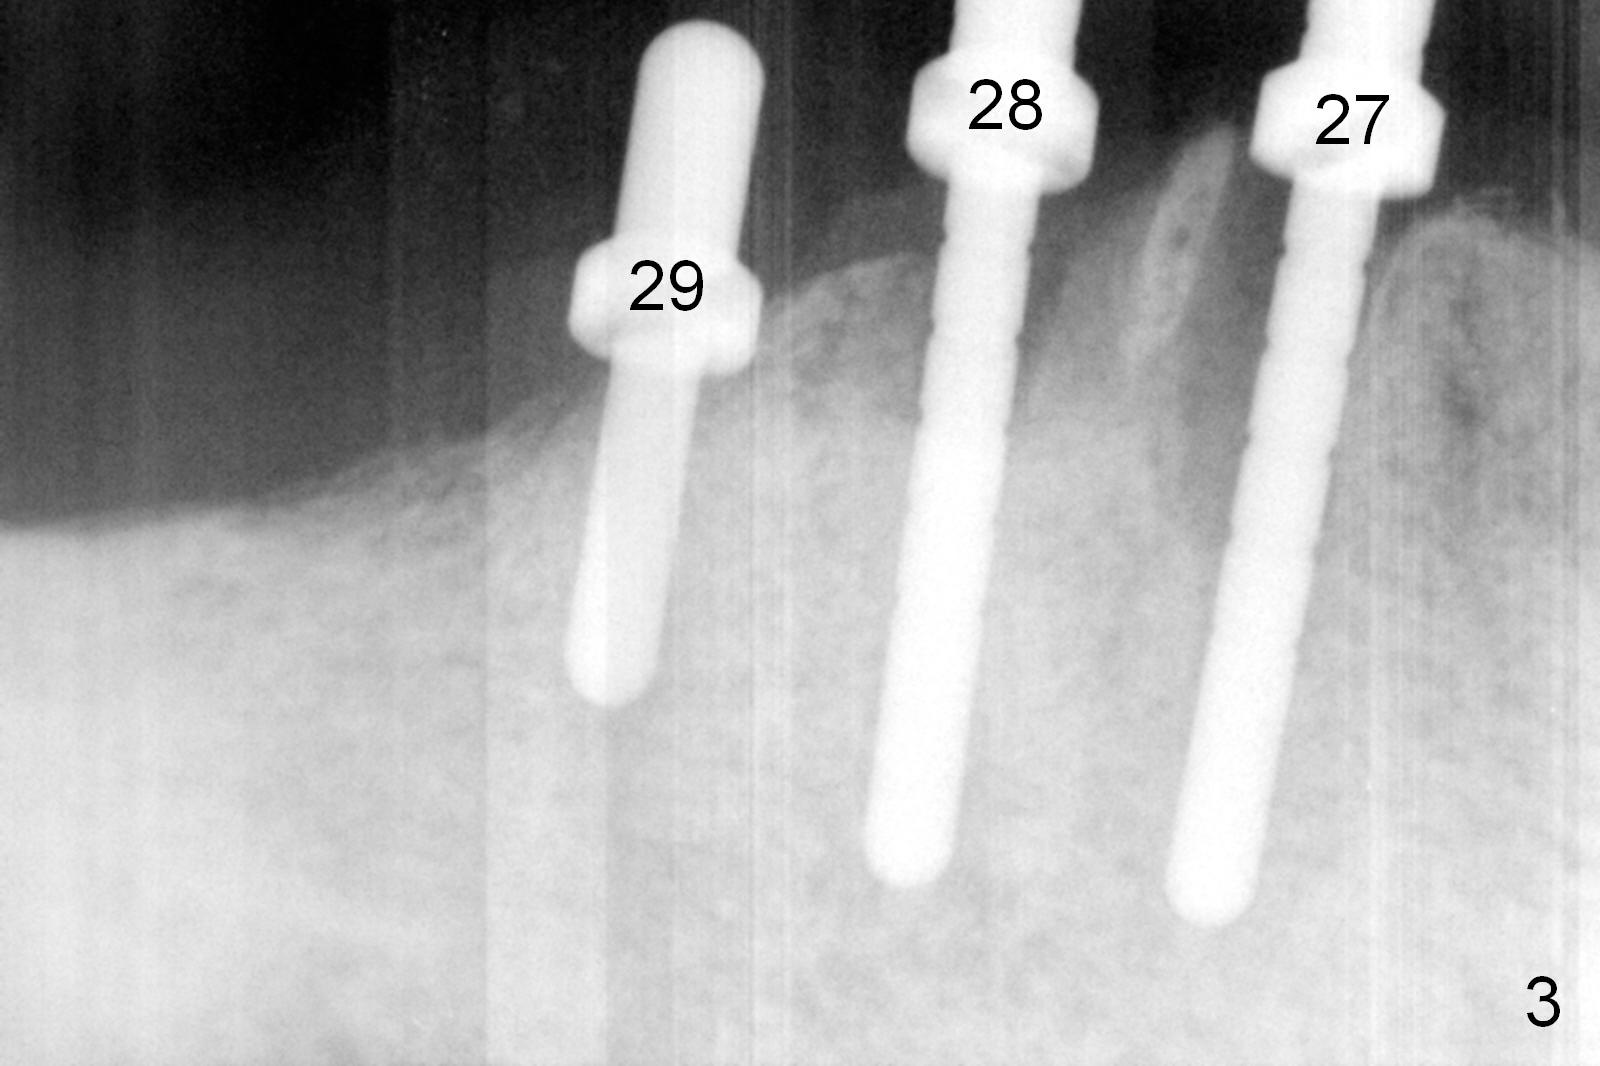

A 86-year-old man returns to office for the lower right quadrant reconstruction with implants. In addition to the immediate ones at the sites of #27 and 28 (Fig.1), how many and where else? The patient reveals that he does not plan to get an implant at the site of #3 (Fig.2). Therefore there is no need for an implant at #30. Preop CT shows that bone width is compromised at #26. So the 3rd site will be #29 (Fig.3,4). All of the 3 implants (4.5x14 mm, 4.5x12, and 4.1x12 mm) achieve primary stability (»55 Ncm). An immediate provisional could be provided, but it seems difficult to close the buccal (Fig.5 B) gaps of #27 and 28 after bone graft with the provisional. In contrast, the gingiva adapts to the implant at #29 well (Fig.6 B). Perio dressing is applied to the abutments (Fig. 7: #27-29), the edentulous space at #26 and the neighboring teeth (#23,24). It would be ideal to apply a non-resorbable membrane to the buccal opening at #27,28 (Fig.8 white line) prior to perio dressing placement. In case of dislodgement of the latter, the membrane is able to keep bone graft in place.